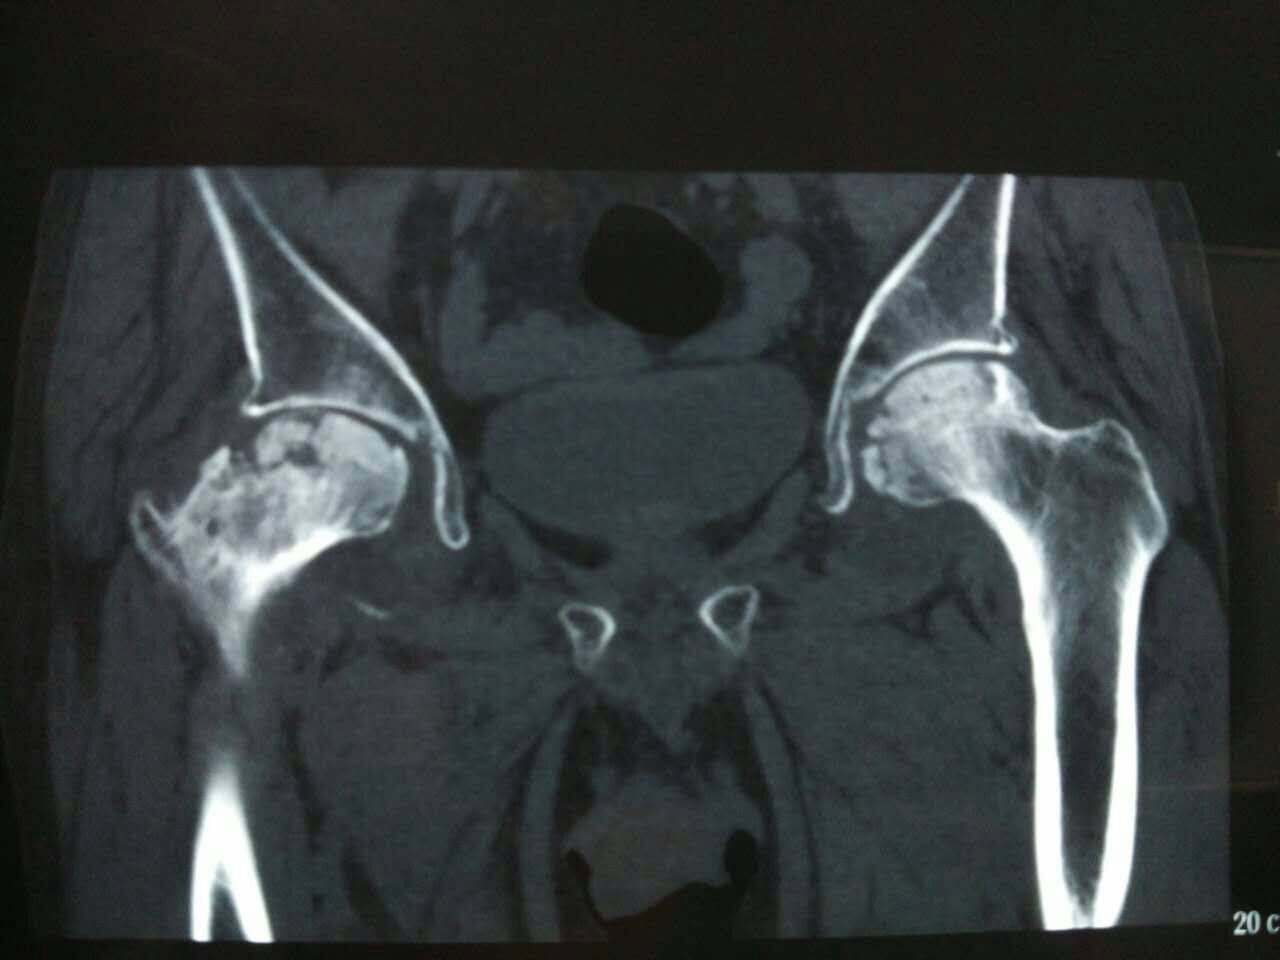

当股骨头坏死处于早期阶段时,三大警示信号常被忽略。首先,髋部隐痛频发,尤其在走路或负重时加剧。其次,腹股沟区域酸痛明显,表现为大腿根部持续性不适,影响日常活动。最后,活动受限突出,如下蹲困难或久坐后起身僵硬。这些股骨头疼痛的症状若不及时察觉,可能延误干预。早期识别这些信号,有助于启动股骨头保守治疗,避免病情恶化。

股骨头坏死早期症状往往表现得比较隐蔽,容易被当成普通的腰腿疲劳。最需要警惕的是三个主要信号:首先是髋部隐痛,这种疼痛感常在腹股沟深处或臀部位置出现,休息时可能减轻但活动后会加重。其次是腹股沟酸痛,具体位置在大腿根靠腹部的地方,走路、爬楼梯时感觉尤其明显。第三个关键信号是活动受限,患者常感觉大腿根部发沉、发僵,像被绳子捆住一样。

这些症状直接影响日常生活。走路时间稍长,大腿根部疼痛就会加剧,甚至出现跛行。做下蹲动作变得非常困难,需要扶着东西才能勉强完成。久坐后起身时,髋关节会感觉异常僵硬,需要活动几下才能缓解。这些日常活动上的不顺畅,正是早期病变发出的重要警示。